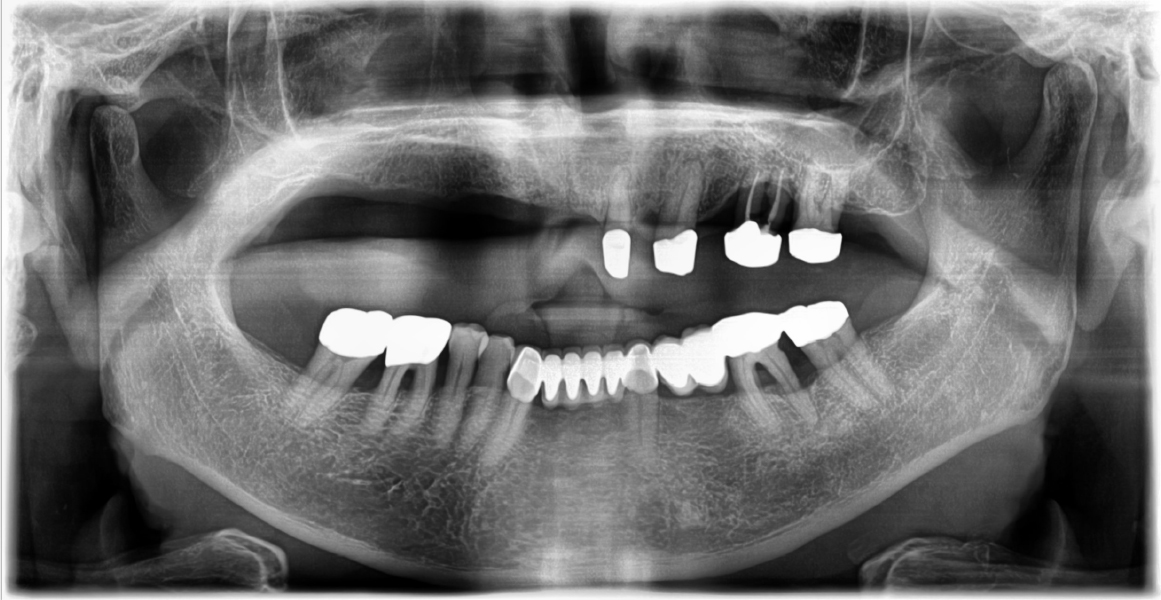

During follow-up appointments, the patient reported a gradual retention loss of the maxillary conus double-crown denture. After 12 years, due to loss of retention, the patient needed a new prosthesis. Clinical and radiographic examinations revealed a severe bone loss in tooth #26 with grade 3 mobility (Fig. 3).

Tooth #26 was evaluated as non-restorable and extracted, and three implants were placed on the right side of the maxilla to allow polygonal support of the new denture. The remaining abutment teeth had no clinical problems; therefore, the original inner gold crown was planned for use. The original maxillary denture was relined using a soft reliner (COE-COMFORT TM ; GC America, IL, USA) and used as a provisional denture (Fig. 4). The definitive restoration was planned as a hybrid telescopic double crown denture with the friction pin method using the remaining inner gold crowns and an additional three implants for abutments.